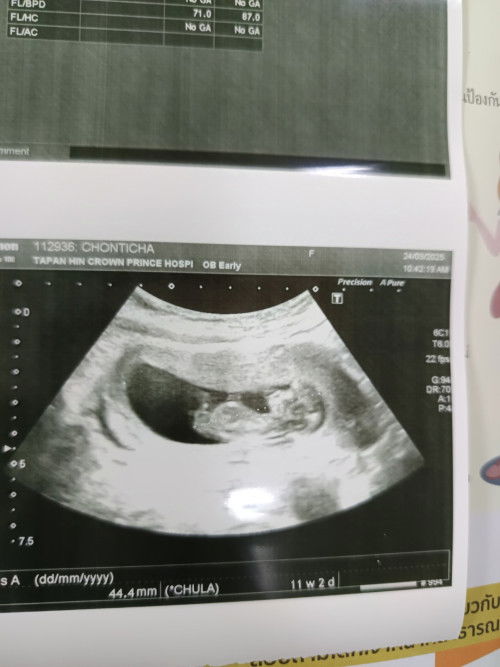

ตอนไปซาวด์ของบ้านนี้11w2dค่ะ วันที่9นัดดูเพศแล้วแต่แม่ว่าลูกยังตัวเล็กอยู่เลย

ซาวด์ตอน 10วีคพอดีค่ะ น้องตัวเล็กมากๆ เเต่ตัวเเค่นี้ ดิ้นโชว์เเล้วค่ะ กำหนดคลอด 16 เมษา คุณหมอเปลี่ยนมาเป็น 14 เมษา 🥰☺️